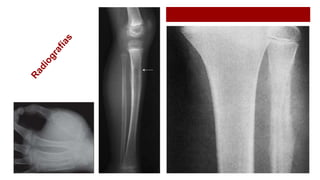

Reacción perióstica:

 (a) Laminar “ en capas de cebolla”.

 (b) Espiculada “ en cepillo”.

 (c) Espiculada “ en rayos de sol”.

 (d) Triángulo de Codman en

Osteosarcoma convencional de metáfisis

Imagenología: Reacción perióstica maligna

RayosdeSol

Capasdecebolla

Espículas finas de hueso debidamente calcificado Delgadas láminas calcificadas paralelas a la

superficie perióstica en la zona tumoral.

Otras imágenes

 Lesiones con destrucción de la cortical ósea.

Otras pruebas de imagen

A: Rx AP. Lesión expansiva de localización subperióstica.

B: Rx AP. Exostosis en cortical de la tibia proximal.

C: TAC axial. Lesión parosteal.